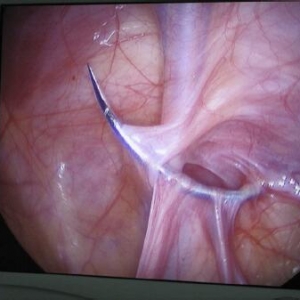

倒钩缝合术在腹腔镜胆囊切除术中胆管损伤修复中的应用——附2例报告Effectiveness of a barbed suture in the repair of bile duct injury during laparoscopic cholecystectomy- Report of two casesAbstract摘要IN ...